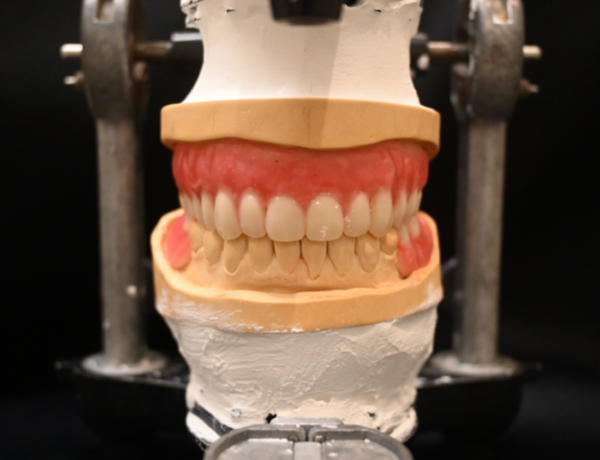

入れ歯の歯を並べる

正面

サイド

保険外(自費)入れ歯完成

上あご

患者さんのかみ合わせやかむ力を考慮して、金属の入れ歯を選択しました。写真を見ると分かると思いますが、入れ歯の金属の部分がとにかく大きく広くとってあります。この金属の設計は、先代の田中久敏に習ったデザインになりますが、口蓋の吸収しない部分は、金属で出来るだけ広く覆って、それ以外の部分は、ピンクのレジンで覆っています。

下あご